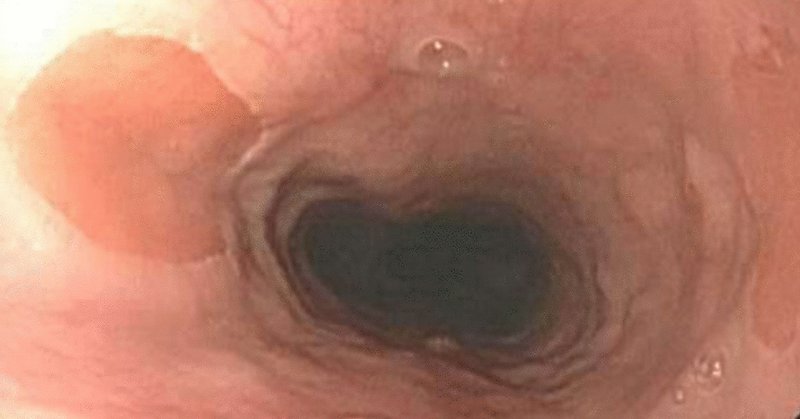

Image of Month: Gastric #cancer metastasis mimicking rectal #IBD This case reminds us to be vigilant about malignancy in IBD. https://t.co/12CuXyVDJc